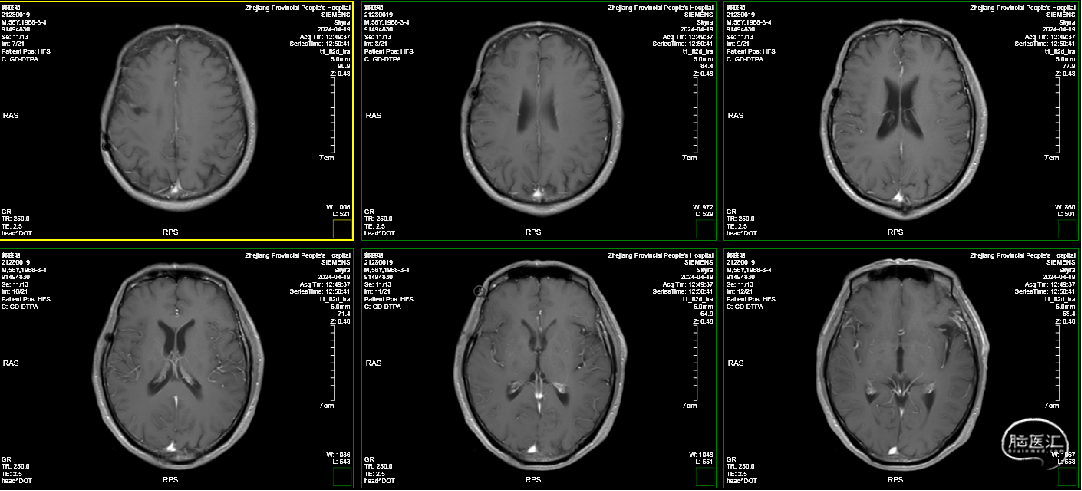

术前MRI: